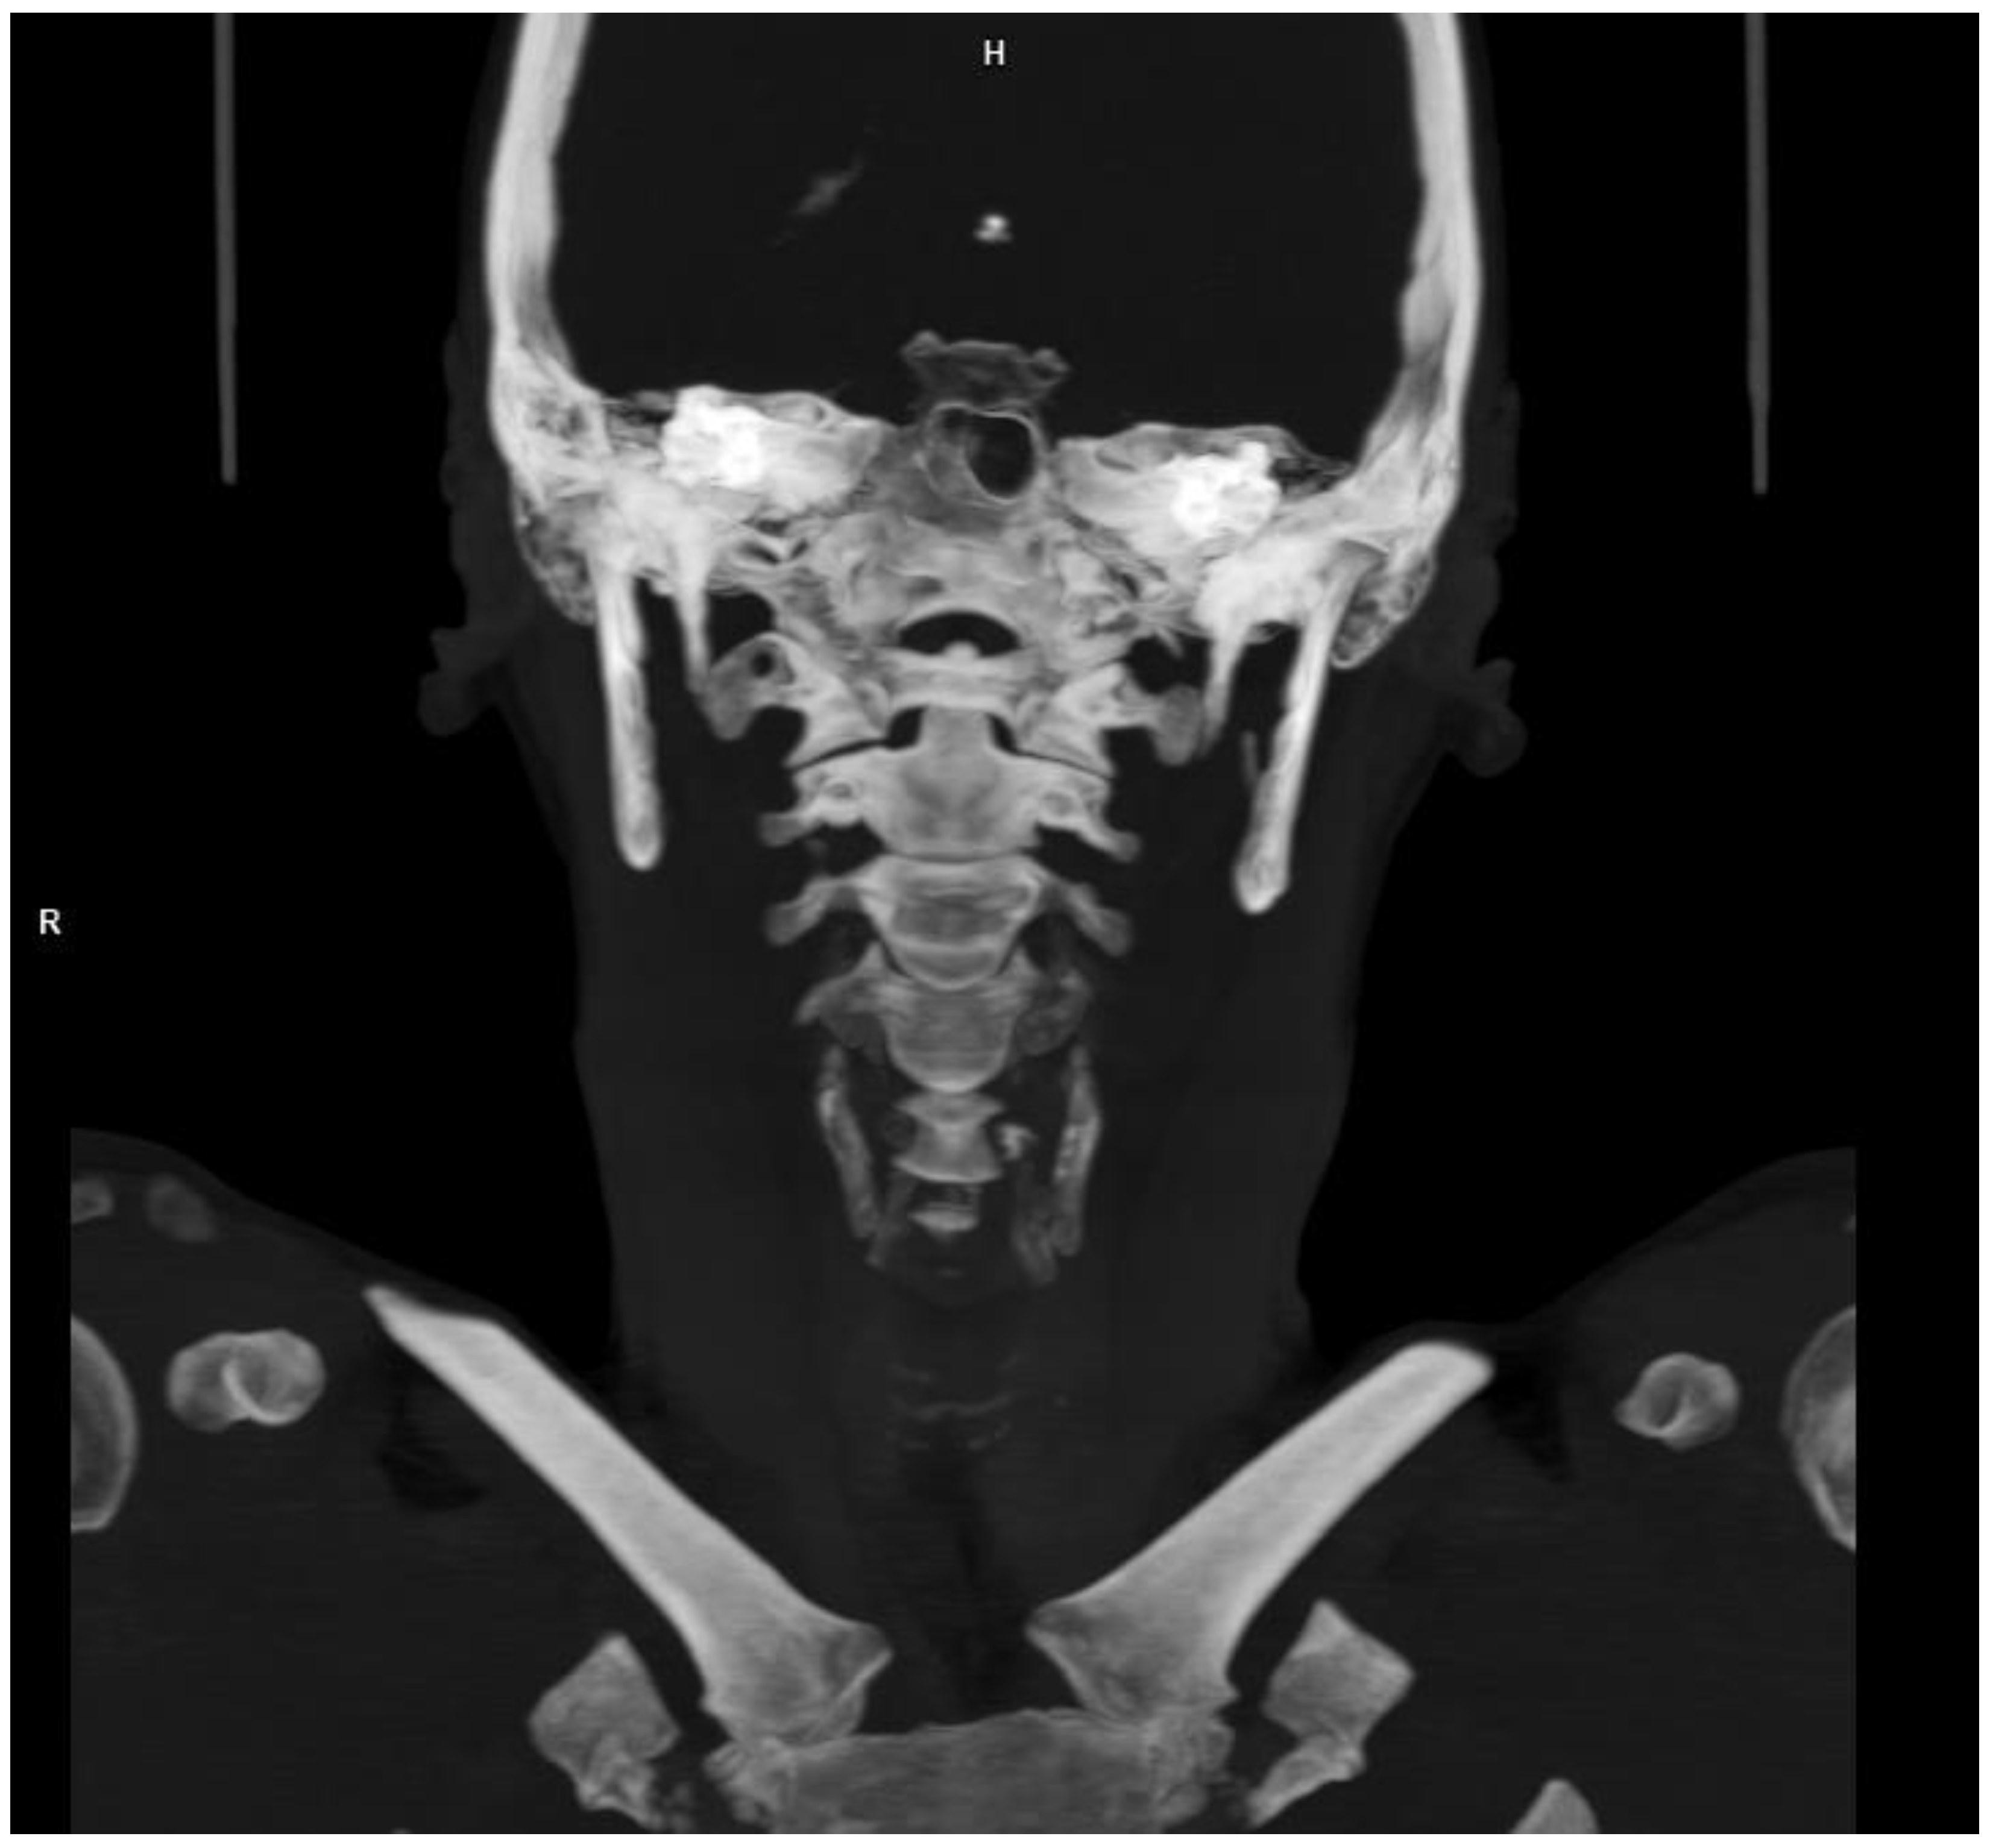

2. Case Presentation

2.2. Diagnosis